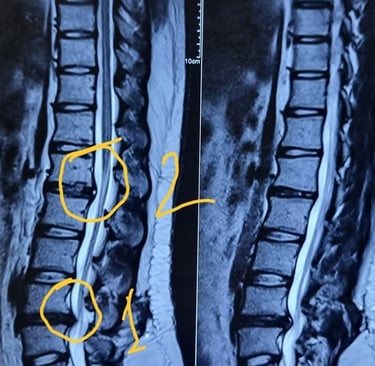

🍀 Diagnosis:

Diagnosis of disc prolapse typically involves a combination of medical history review, physical examination assessing reflexes and strength, and imaging studies such as MRI or CT scan to visualize the spine and confirm the location and severity of the prolapsed disc.